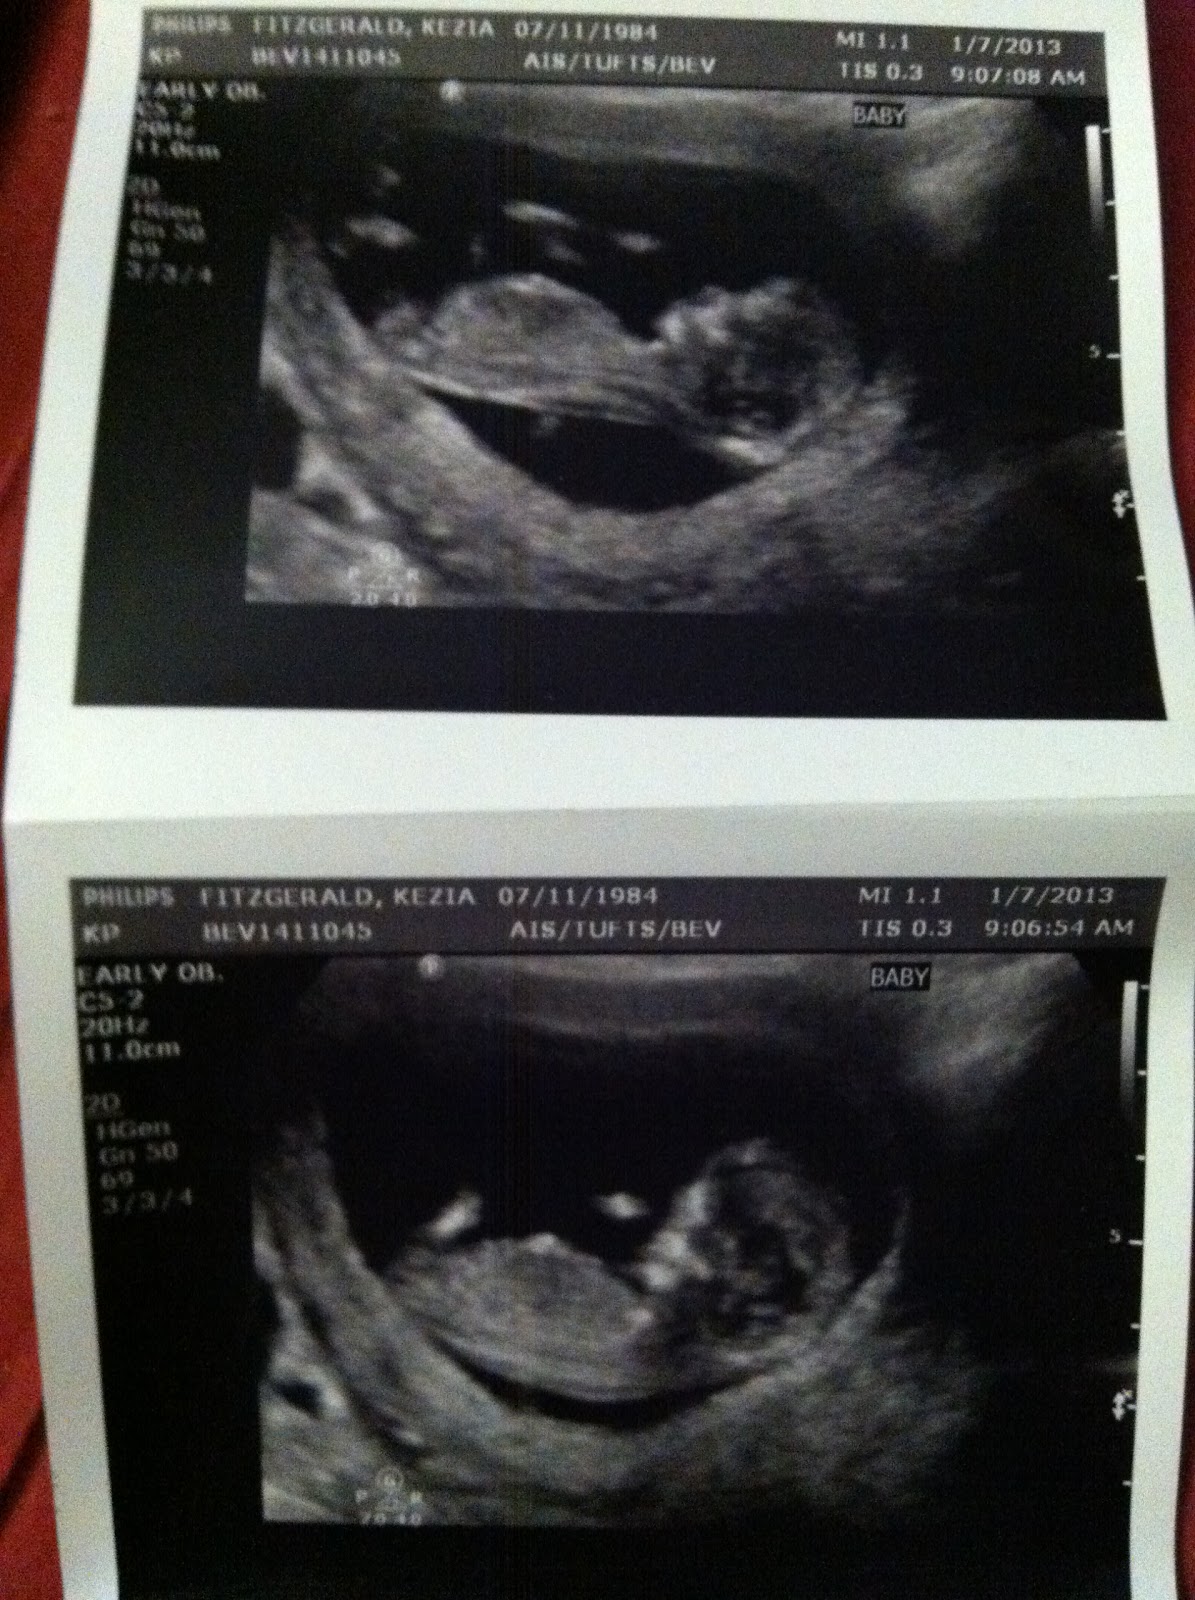

Well, Mike a little bit let it out of the bag, so I guess I better put it out there... Saoirse is going to be a big sister!

Both the baby and I are doing well. We go for regular check ups and all the doctors see no complications. I have a team of people looking over everything, and everyone has been amazingly supportive. It's been a hard time emotionally, and I've had some trouble connecting with being pregnant again, but we are working through it, and deep down we are truly excited and happy. We know Saoirse would have loved being a big sister, and she would have been a great one.